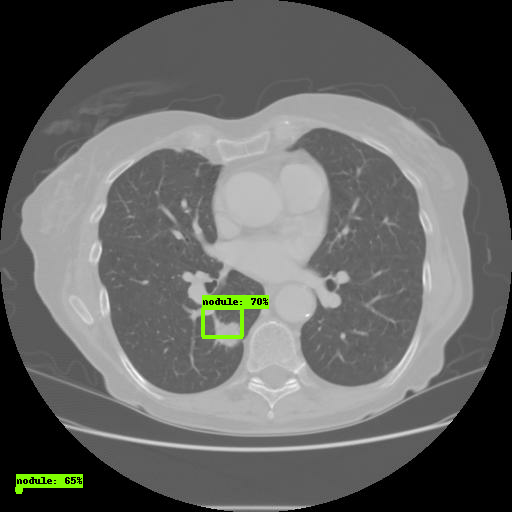

В рамках своего проекта мы постараемся добиться обнаружения легочных узлов при помощи датасета LUNA. Координаты узлов уже были известны, а потому создание CSV-файлов не составляло труда. Для обнаружения узлов мы используем 6 координат, показанных ниже:

Откройте ссылку через браузер. Во вкладке Images вы увидите результаты работы модели: